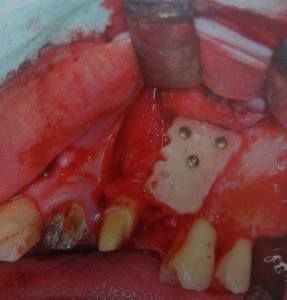

抜歯してインプラントするには、ブロック骨移植、歯肉移植が必要です。

こんな感じに骨移植が必要です。

歯茎も感染で溶けてしまったので、上顎から歯肉を切り取って移植しないといけません。